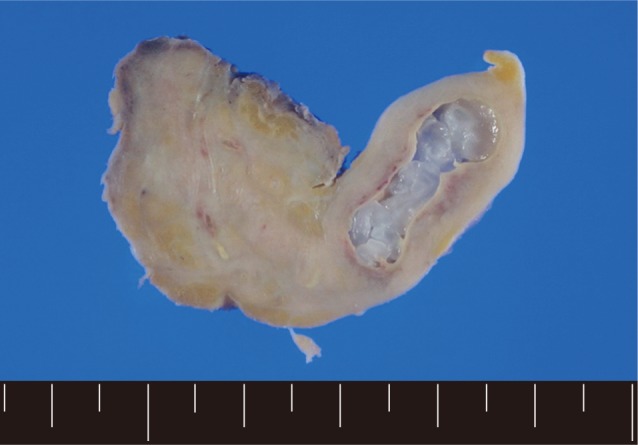

A 56-year old male visited our out-patient clinic for pancytopenia. Bone marrow biopsy and karyotype analysis showed myelodysplastic feature with 14% blast count and normal karyotype, indicating MDS, refractory anemia with excessive blast. He received 4 cycles of decitabine treatment during searching for matched unrelated donor, and partial response was shown. Allogeneic peripheral HSCT with myeloablative conditioning regimen consisting of busulphan and cyclophosphamide was performed from a HLA full-matched unrelated donor. However, at day 5 post-HSCT, 5 cm-sized hard and movable mass in the left scrotum and multiple palpable lymph nodes was detected at the left inguinal area. Pelvic magnetic resonance imaging and computed tomography were done and it was suspected initially as a myeloid sarcoma in the subcutaneous fat layer of the left scrotum and pathologic lymphadenopathy at the left inguinal area (Fig. 1). In order to confirm the diagnosis, gun biopsy was done on the left scrotal mass to avoid bleeding due to thrombocytopenia after HSCT. The result of the gun biopsy was inflamation of fibrovascular soft tissues with extensive interstitial eosinophilic infiltrations without evidence of malignancy. Persistent peripheral eosinophilia was also developed after HSCT. Subsequently, IgG antibody tests for paragonimiasis, cysticercosis, sparganosis, and clonorchiasis were done, and the results were positive for sparganosis and negative for all others. We re-evaluated the patient's past history and found out that he had swam in the river and ate raw fish, cow liver, and pork meat frequently when he was young. For a next step, excision biopsy was done as an approach for therapeutic diagnosis after recovery of thrombocytopenia. The cut surface of the biopsied specimen showed a cyst filled with whitish and myxoid tissues, measuring 2.0×0.6 cm (Fig. 2). The biopsy result was severe acute and chronic inflammation and fibrosis with a sparganum worm (Fig. 3). He was discharged after complete wound healing and stabilization of the post-HSCT condition.